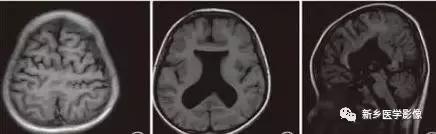

8.胼胝体发育不良

在脑发育腹侧诱导晚期,新形成的端脑嘴侧壁的背侧部分增厚、内陷,向后沿尚未完全发育的大脑半球间裂延伸。两个月后形成一个连合即胼胝体纤维的细胞框架,该细胞框架形成后胼胝体相应部分立即发育。膝部先发育。然后是体部、压部.位于胼胝体膝部后下方的胼胝体嘴最后发育。如果胼胝体发育过程中出现有害因素,就有可能导致胼胝体发育不良.表现为完全缺如或部分缺失。常表现为膝部存在或膝部和体部存在。压部和胼胝体嘴缺失。

胼胝体发育不良可见单独发病,但更常见的是伴有中枢伸经系统的其他畸形,包括胼胝体周围脂肪瘤、脑膨出、交通性脑积水Chaiarii畸形、Dandy-Walker囊肿、脑裂畸形等。临床上可无症状或仅有轻度临床症状,临床检查可见眼距过宽、大头畸形、智力发育迟滞等。胼胝体缺失时,MR冠状位上侧脑室前角呈新月形表现,侧脑室体部分离,呈垂直状平行走行。